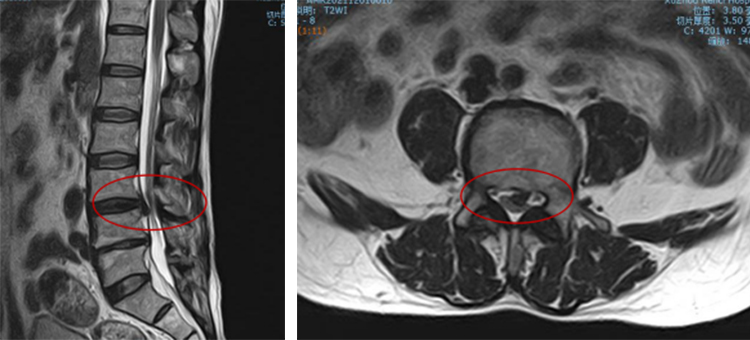

63岁的李大爷(化名),一周前搬东西的时候,起身发现腰背部剧烈疼痛了起来,因为十五年前做过腰椎间盘髓核摘除手术,知道腰肯定出问题了,就赶紧卧床休息。结果休息几天,不仅疼痛没有好转,左腿还开始出现疼痛麻木。李大爷眼见情况不妙,赶紧在家人的陪伴下,前来betway在线登陆脊柱科就诊。经脊柱科张冶副主任医师仔细检查后,李大爷被诊断为腰椎间盘突出症(椎间盘脱出),必须尽快手术治疗。

术中在C形臂X光机透视定位L3/L4椎间隙中点,沿导向器做1cm手术切口,内镜观察下,利用超声骨刀切除部分L3下椎板下关节突,显露神经根及脱出的髓核,髓核钳取出脱出游离的髓核组织,手术顺利完成。实现了手术的微创化、精准化、智能化、可视化。